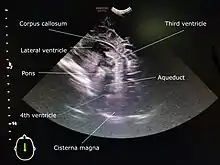

A 5 to 7.5 MHz probe is used to scan deeper structures in the brain. A 7 to 12 Mhz probe is used for scanning superficial structures for detecting lesions between the brain and the skull, superior sagittal sinus thrombosis, cerebral oedema, and evaluating the structures of sulci and gyri.[4]

A standard cranial ultrasound examination usually involves recording of approximately 11 views of the brain from different angles, six in the coronal plane and five in the sagittal and parasaggital planes.[7] This allows all parts of the ventricles and most of the rest of the brain to be visualised.

While the anterior fontanelle is the most commonly used acoustic window for cranial ultrasounds, more advanced operators may gain additional views, especially of posterior fossa structures, by using the mastoid fontanelle, the posterior fontanelle and/or the temporal window.[8]

Other refinements of cranial ultrasound technique include serial measurement of the width of the lateral ventricles ("ventricular index") to monitor suspected ventricular dilatation and colour Doppler to assess blood flow.